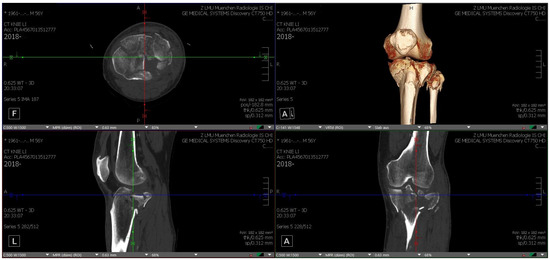

Each TPF was presented in three steps to the participating surgical specialists in trauma surgery. First by CT, including 3D CT reconstruction (software: Visage 7.1.16—Visage Imaging, San Diego, CA, USA; Figure 1), subsequently on MR glasses (Figure 2), and finally as a 3D-printed model (Figure 3).

Figure 2.

Mixed-reality glasses with holograms (axial and frontal) of fracture 1.